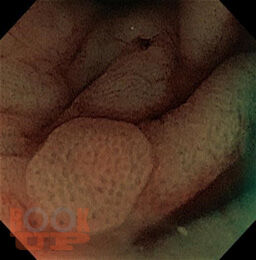

Эпителиальные образования желудочно-кишечного тракта

В предлагаемом учебном пособие представлены сведения об этиологии, морфологии и патогенезе эпителиальных образований ЖКТ, методике эндоскопического удаления полипов толстой кишки. Пособие содержит тестовые задания для самоконтроля.

Учебное пособие предназначено для использования при реализации основных профессиональных образовательных программ высшего образования по направлениям подготовки клинических ординаторов 31.08.70 «Эндоскопия», 31.08.67 «Хирургия».